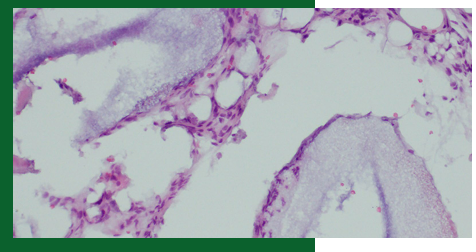

Abstract: In preimplantation regenerative surgery of the alveolar ridges, a widely used methos of reconstructing the bone of the lateral maxillary part of the process is to lift the floor…